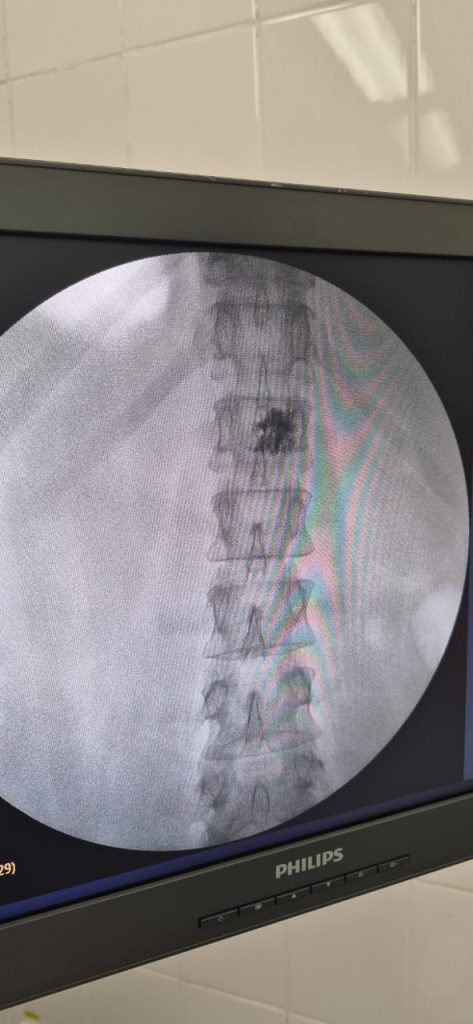

Бүгінде гемангиоманы емдеудің тиімді және қауіпсіз әдістерінің бірі — перкутандық вертебропластика. Бұл — теріге кішкентай тілік арқылы жасалатын кіші инвазивті процедура. Операция кезінде әлсіреген омыртқа денесіне арнайы медициналық цемент енгізіледі. Ол омыртқаны бекітіп, гемангиоманың өсуін тоқтатады және ауырсынуды жылдам басады. Процедура шамамен 20–30 минутқа созылады, жалпы жансыздандыру жасалады, ал науқас бірнеше сағаттан кейін-ақ өздігінен жүріп тұра алады.

Тараз қалалық көпбейінді ауруханасында мұндай операциялар күн сайын тәжірибелі нейрохирургтармен заманауи құрал-жабдықтар арқылы жүргізіледі. Ең маңыздысы — вертебропластика МӘМС бойынша, яғни көрсетілімдері болса, науқас үшін тегін жасалады. Егер МРТ кезінде сізден гемангиома анықталса немесе беліңіз ауырып, аяқтарыңызда әлсіздік сезілсе, уақыт созбай маманға қаралған жөн. Ерте диагностика мен дер кезінде емдеу асқынулардың алдын алуға және өмір сапасын сақтауға мүмкіндік береді.